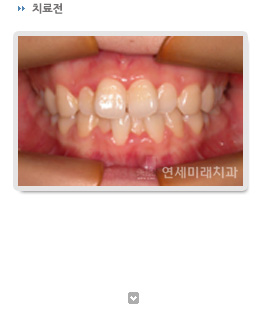

¾Õ´Ï°¡ °Å²Ù·Î ¹°¸®´Â °æ¿ìÀÇ Ä¡·á¿¡ ÀÖ¾î¼ Áß¿äÇÑ °ÍÀº ¿øÀÎÀÌ °ñ°Ý°ü°è¿¡ ÀÖ´À³Ä, ±³ÇÕ°ü°è¿¡ ÀÖ´À³Ä ÇÏ´Â °ÍÀÔ´Ï´Ù. û¼Ò³âÀÇ °æ¿ì¿¡ ¼ºÀå´Ü°è¿¡ µû¶ó¼ ´Ù¾çÇÑ Á¢±Ù¹æ¹ýÀÌ ÀÖÀ¸¸ç, ¿øÀÎ ºÐ¼®¹× ÀÜ¿© ¼ºÀå·® Æò°¡ ÈÄ Ä¡·á¹æ¹ýÀ» °áÁ¤ÇÏ°Ô µË´Ï´Ù. ¾Õ´Ï°¡ °Å²Ù·Î ¹°¸®´Â ¼ºÀå±â ¾î¸°À̵éÀÇ °æ¿ì, Ä¡°ú¿¡ ³»¿øÇؼ °Ë»ç¸¦ ¹Þ¾Æ¾ßÇÏ´Â ½Ã±â´Â »çÁø¿¡¼ º¸½Ã´Â°Í ó·³ °Å²Ù·Î ¹°¸®´Â ¿µ±¸ÀüÄ¡°¡ ¹ß°ßµÈ Á÷ÈÄÀÔ´Ï´Ù. ¿Ö³ÄÇϸé ÀÌ ½Ã±â¿¡´Â °Å²Ù·Î ¹°¸®´Â ±³ÇÕ°ü°è ÀÚü°¡ ¾Æ·¡ÅÎÀÇ °ñ°ÝÀûÀÎ °ú¼ºÀåÀ» ÃËÁø½ÃŰ´Â ȯ°æÀÌ µÇ±â ¶§¹®ÀÔ´Ï´Ù. ¿µ±¸ÀüÄ¡´Â ¸¸ 7¼¼ ¹«·Æ¿¡ ¸ÍÃâµÇ´Âµ¥, ÀÌ ¶§ °üÂûµÇ´Â ÀüÄ¡ºÎ ¹Ý´ë±³ÇÕÀº °£´ÜÇÑ ¹æ¹ýÀ¸·Î ÇØ°áÇÒ ¼ö ÀÖ´Â °æ¿ì°¡ ¸¹½À´Ï´Ù.

°Å²Ù·Î ¹°¸®´Â ¿øÀÎÀÌ ½ÉÇѰñ°ÝÀûÀÎ ¹®Á¦¸¸ ¾Æ´Ï¶ó¸é ¹ÛÀ¸·Î º¸ÀÌ´Â ÀåÄ¡ ¾øÀ̵µ 6°³¿ù¿¡¼ 1³â »çÀÌ¿¡ »çÁø¿¡¼ º¸½Ã´Â Áõ·Ê¿¡¼ ó·³ ¹Ù¶÷Á÷ÇÑ ±³ÇÕ°ü°è¸¦ ´Þ¼ºÇÒ ¼ö ÀÖ½À´Ï´Ù.